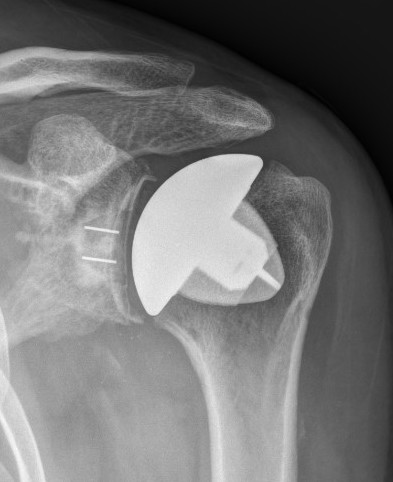

Hemiarthroplasty / TSR